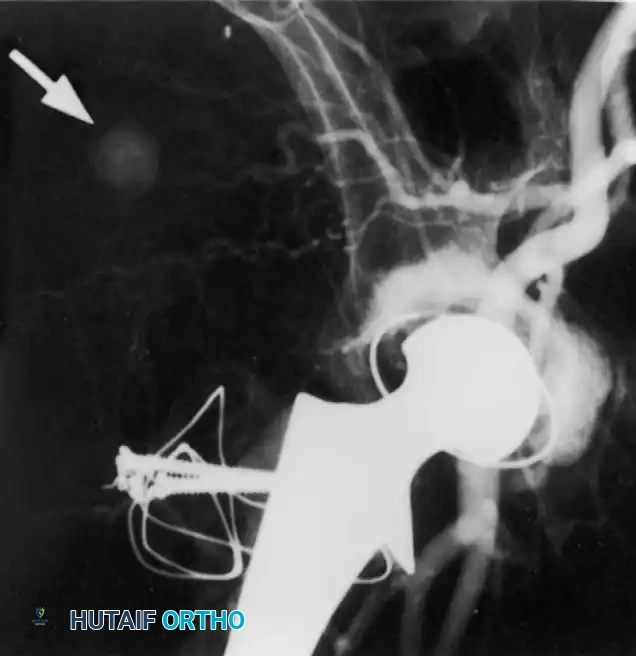

Late bleeding (≥ 1 week postoperatively) may occur secondary to a false aneurysm. In such cases, arteriography is required for the precise identification of the affected vessel, often followed by therapeutic embolization.